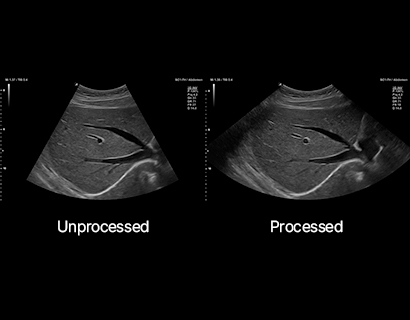

SL3-19H

X+ Crystal Signature™ linear transducer(3~19MHz)

Application:

MSK, Vascular, Small Parts, Breast, TCD, Abdomen, Pediatric, Gynecology, Obstetrics, EM